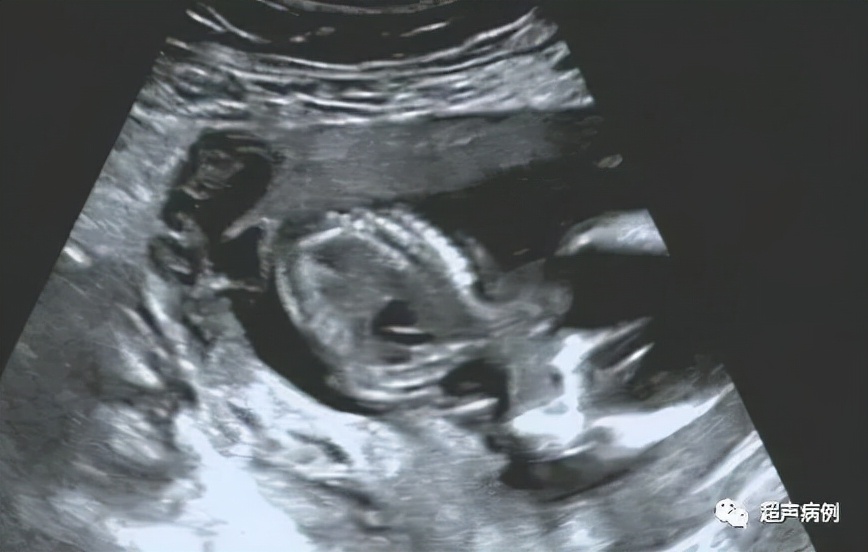

此时我的设备远场增益很强,调整增益后,终于在孕妇子宫前壁下段与胎膜之间发现了节育器。